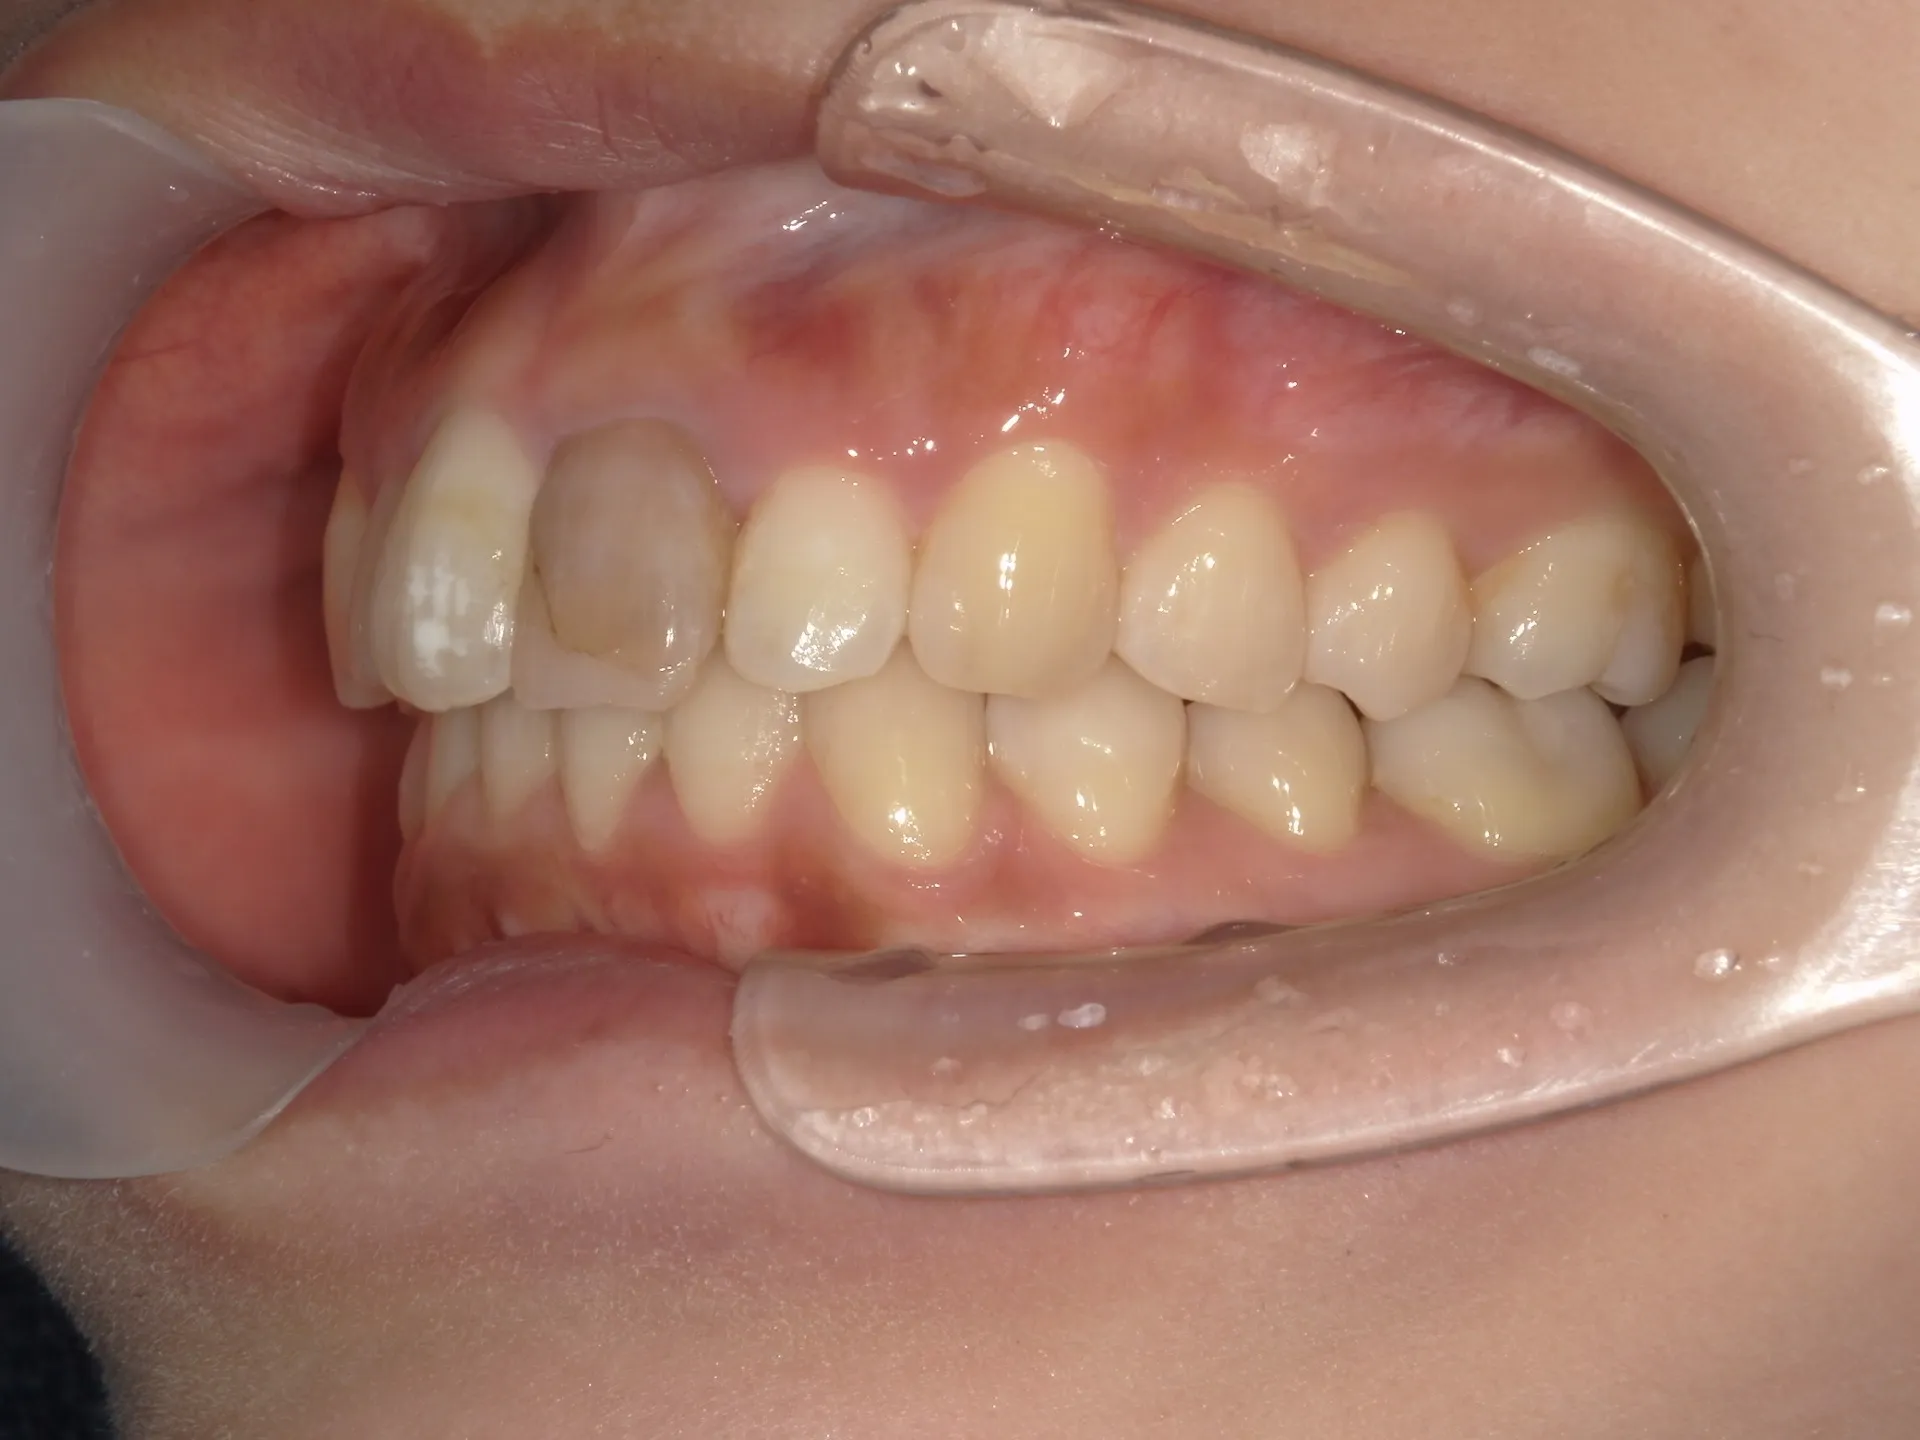

大きく飛び出してしまった前歯の矯正と変色の治療を希望された症例をご紹介いたします。